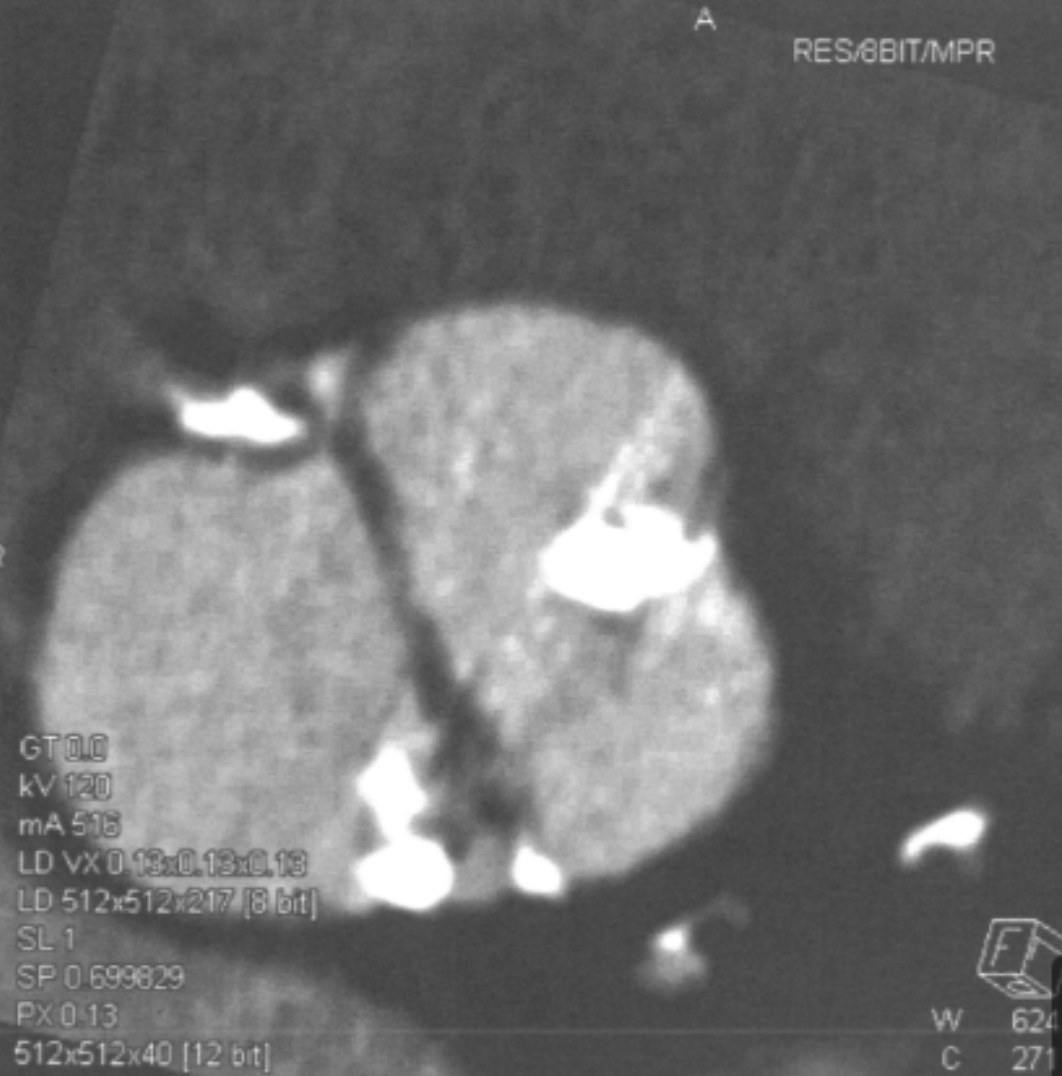

What are the characteristics of chronic infarct by cardiac CT?